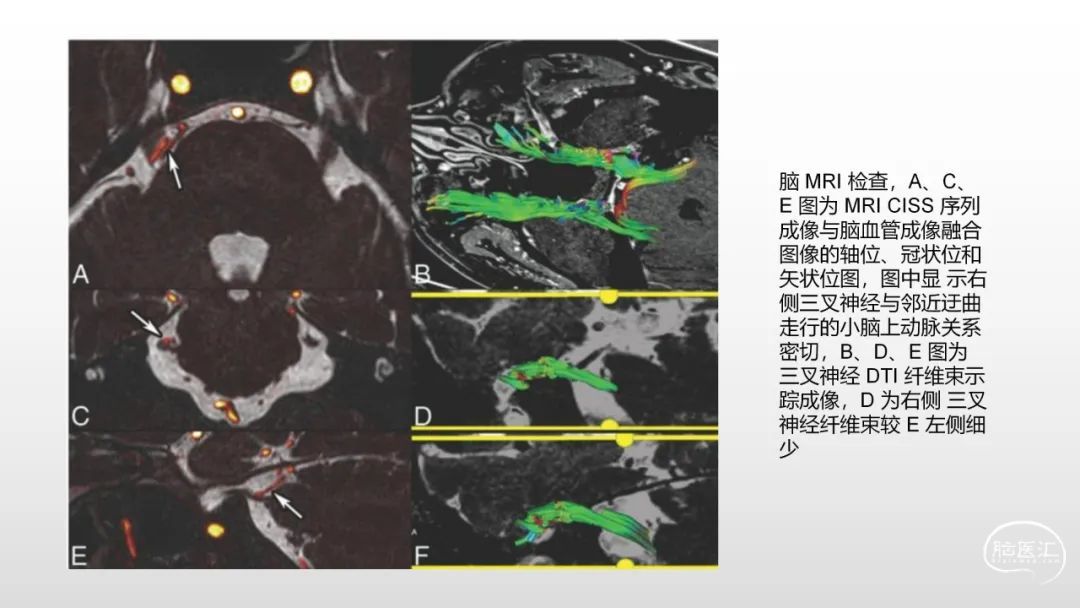

颅脑影像诊断基础知识讲座:《脑血管病》之出血、血管畸形、动脉炎及神经卡压